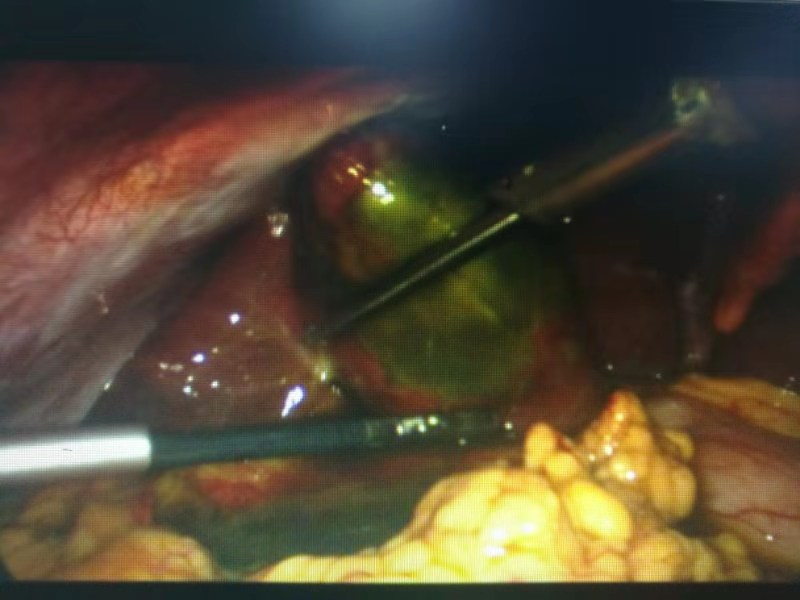

有了周詳?shù)挠媱潱?jīng)過充分的術(shù)前準備,手術(shù)開始了。從腹腔鏡下發(fā)現(xiàn),患者膽囊底部壞疽穿孔,膽囊周邊有膽汁滲出。一個小時左右,壞疽膽囊和膽結(jié)石被成功取出。

患者術(shù)中照片